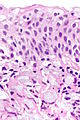

Microscopic

Features:

- Signet ring cells resemble signet rings.

- They contain a large amount of mucin, which pushes the nucleus to the cell periphery.

- The pool of mucin in a signet ring cell mimics the appearance of the finger hole.

- The nucleus mimics the appearance of the face of the ring in profile.

- Signet ring cells are typically 2-3x the size of a lymphocyte.

- Smaller than the typical adipocyte.

- Often have a crescent-shaped or ovoid nucleus.

- Capillaries sectioned on their lumen have endothelial cells - the nuclei of these are more spindled.

Note:

- SRCs are usually close to friend, i.e. they are adjacent to another SRC.

- This helps differentiate SRCs from capillaries sectioned on their lumen.

- The mucin is often clear on H&E... but maybe eosinophilic.